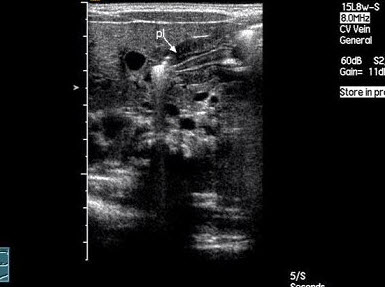

34、单项选择题

男,11岁,右侧阴囊空虚,左侧睾丸可触及,右侧腹股沟区可探及低回声肿块,如图所示,考虑为()

A.隐睾

B.淋巴结

C.腹股沟疝

D.腹股沟肿瘤

E.以上都不是